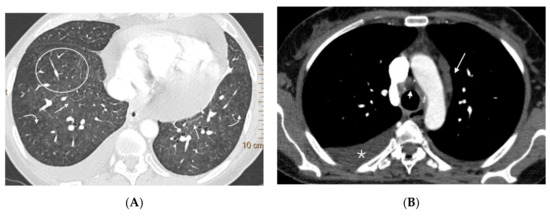

Figure 5.

Forty-seven-year-old woman with sporadic PVOD and three typical findings. (A) Ground glass parenchymal involvement with central geographic distribution (circle) and peripheral centrilobular (curved arrows). Septal lines in basal regions of both lungs (straight arrows); (B) mediastinal lymphadenopathy in the lower right paratracheal location (short arrow) and prevascular (arrow). Right pleural effusion (asterisk).